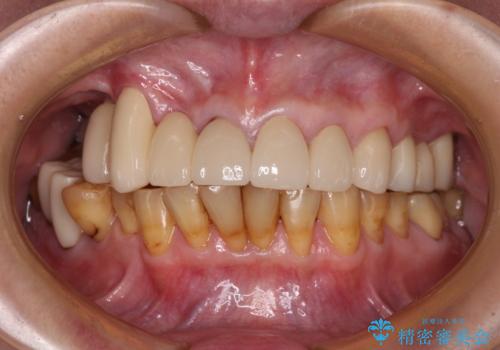

臼歯部は痛みが生じている歯に絞って処置を行い、それ以外については手を加えず、現状維持を心がけることとしました。

前歯部については抜歯が必要な歯を抜歯し、インプラントやブリッジなどにより補綴治療を行うこととしました。

臼歯部は今後抜歯が必要となった際に、インプラントにより咬合を構築していくこととしました。今回の治療においても、今後の臼歯部の治療に対応できるよう治療計画を立案しています。